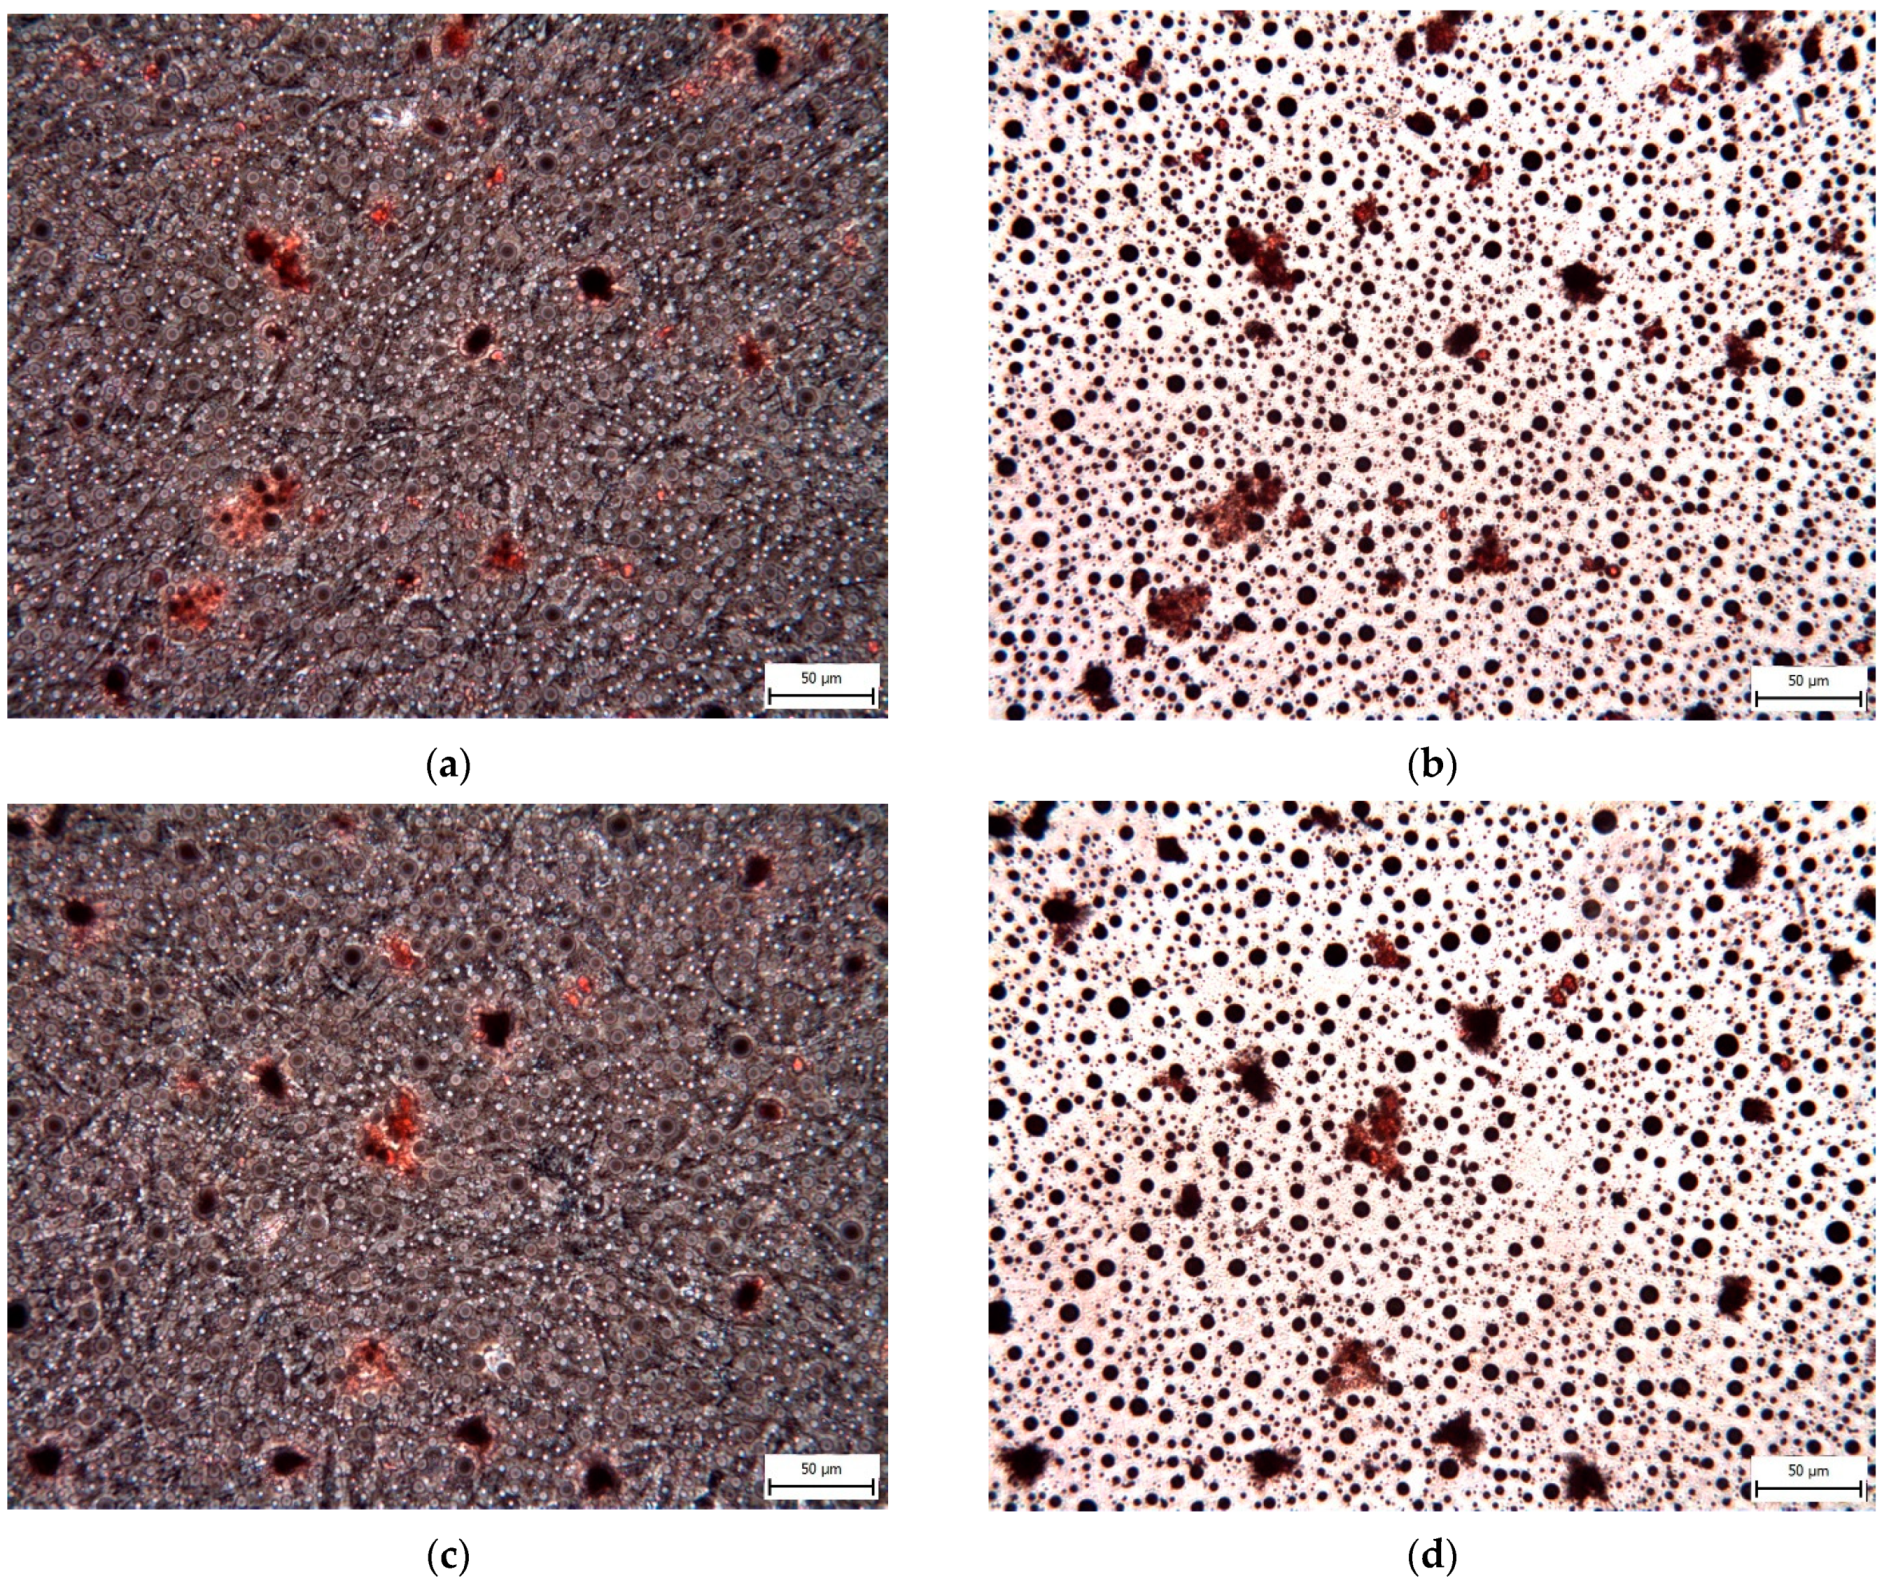

3.4. Effect on hNDP-SC Multipotency

2.6.3. Adipogenic Differentiation In Vitro

3.1. Effect on hNDP-SC Proliferation and Viability

3.2. Effect on hNDP-SC Phenotype Profile and Specific Factor Expressions